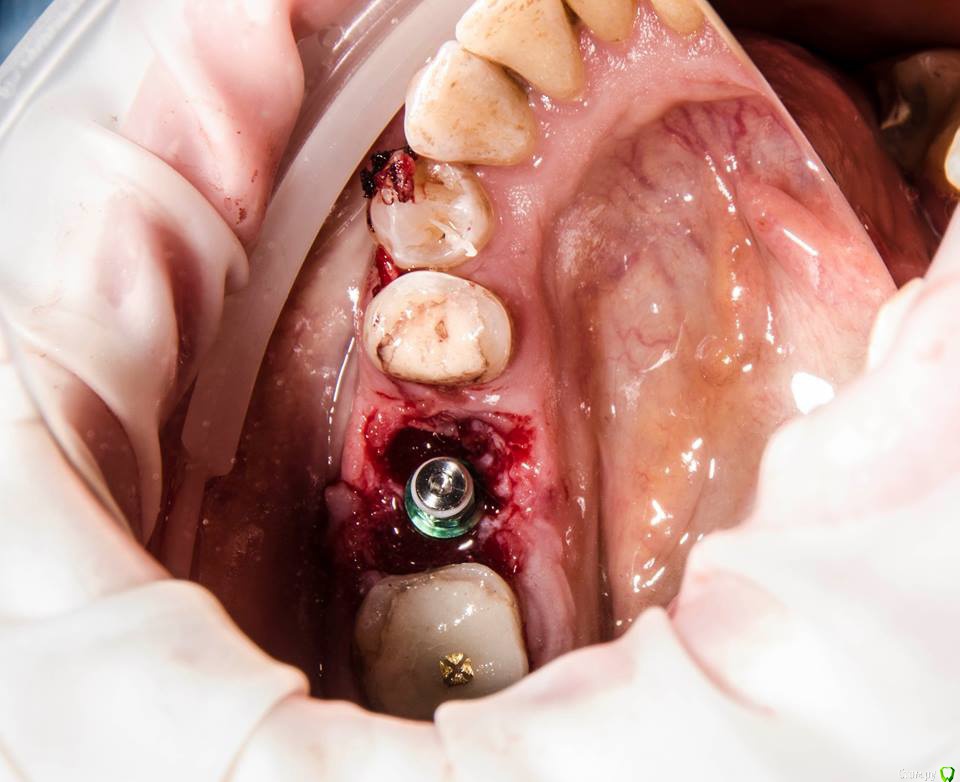

kamranchick Опубликовано 29 марта, 2016 Поделиться Опубликовано 29 марта, 2016 Не надо в рану альвостаз пихать, по опыту он только мешает заживлениюОлег, как вы думаете, можно ли так поступать? тут мембраны нет, только алвостаз Ссылка на комментарий